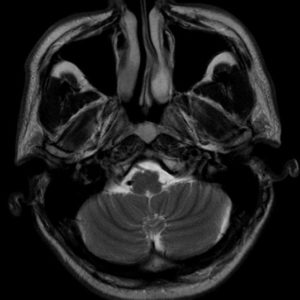

U dây VIII

Lượt xem: 140» 24-11-2018 -

U dây VIII

Lượt xem: 131» 24-11-2018 -

U dây VIII

Lượt xem: 143» 24-11-2018 -

U dây VIII

Lượt xem: 155» 24-11-2018 -